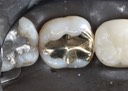

Joe Cha #20 amalgam removal